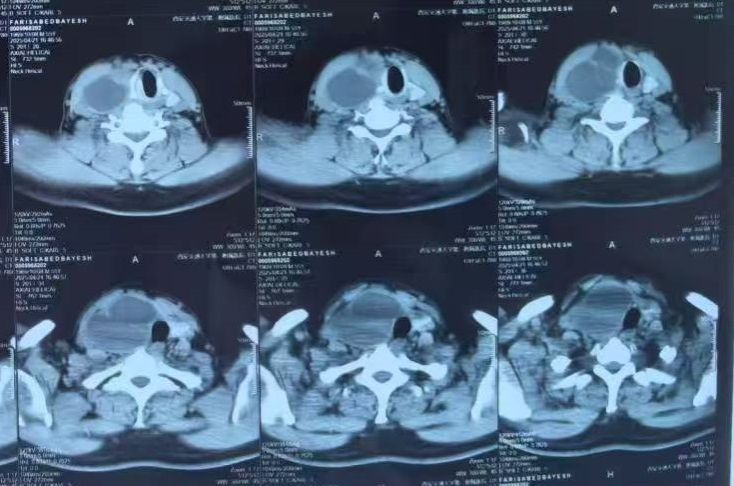

一带一路沿线国家伊拉克籍友人Faris先生50多岁,因经济交流长期来往于伊拉克-中国等一带一路国家从事贸易活动。之前发现脖子上包块3年,但一直未在意。近期发现包块增大明显伴有肿胀不适,伊拉克当地医院也做了检查,带着介绍信来我院,就诊于内分泌科董鹏副教授。进一步行甲状腺彩超和颈部CT检查后发现甲状腺右侧叶包块较大,并压迫气管左侧移位明显。董鹏副教授立即和老年普外科大明宫院区王志东主任联系,安排住院准备手术。

手术团队术前进行了多学科讨论和交流。医用超声科姜珏副主任看过彩超和颈部CT后认为,甲状腺右侧叶包块肿大明显,压迫气管左侧移位,尽管伊拉克当地医院建议来我院射频消融,但容易复发,手术切除是首选。内分泌科董鹏副教授表示术前甲状腺功能基本正常,降钙素和甲状旁腺素也正常,可以实施手术,术后应用左甲状腺片替代治疗,定期复查。老年普外科进行科室内讨论后认为,术前各项检查无麻醉手术禁忌,尽管甲状腺右侧叶肿大明显,但以囊性为主,可以实施完全腔镜下甲状腺肿块切除,解除气管压迫隐患,满足Faris先生颈部无刀痕微创手术的愿望。